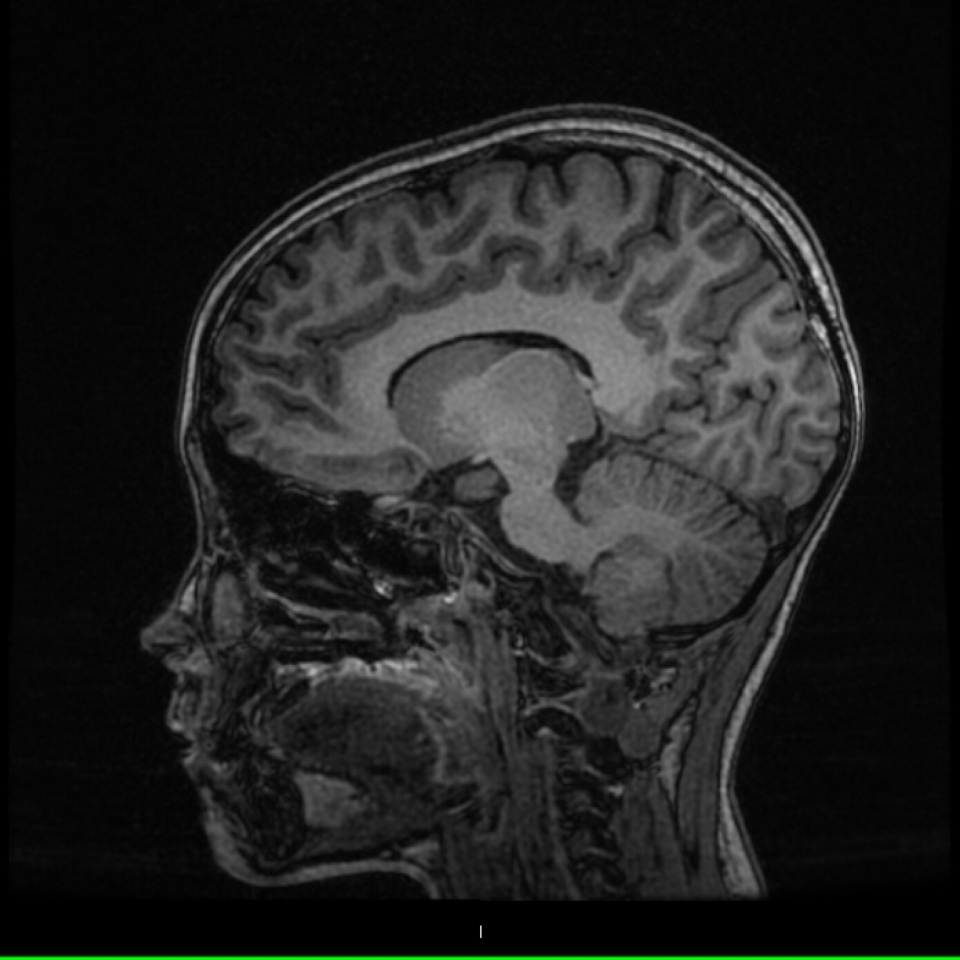

How We Diagnose Craniopharyngioma Effectively

Our diagnostic approach primarily relies on advanced imaging techniques such as MRI and CT scans. These imaging studies provide valuable insights into tumor composition and its effects on adjacent brain structures. We conduct comprehensive assessments to ensure accurate diagnosis and to determine the best treatment options based on each patient’s individual case. Patients at our center benefit from our commitment to utilizing the latest diagnostic technology.